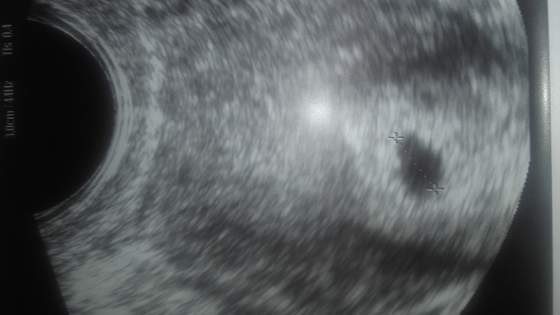

20151207_203833.jpgTo jest mój piękny pęcherzyk 5,6 mm:) Zdjęcie z 07.12:)